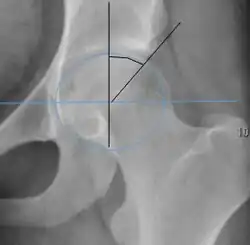

| Measurement | Image | Target | Normal value |

| Center-edge angle of Wiberg |  |

The superior-lateral coverage of the femoral head. | |